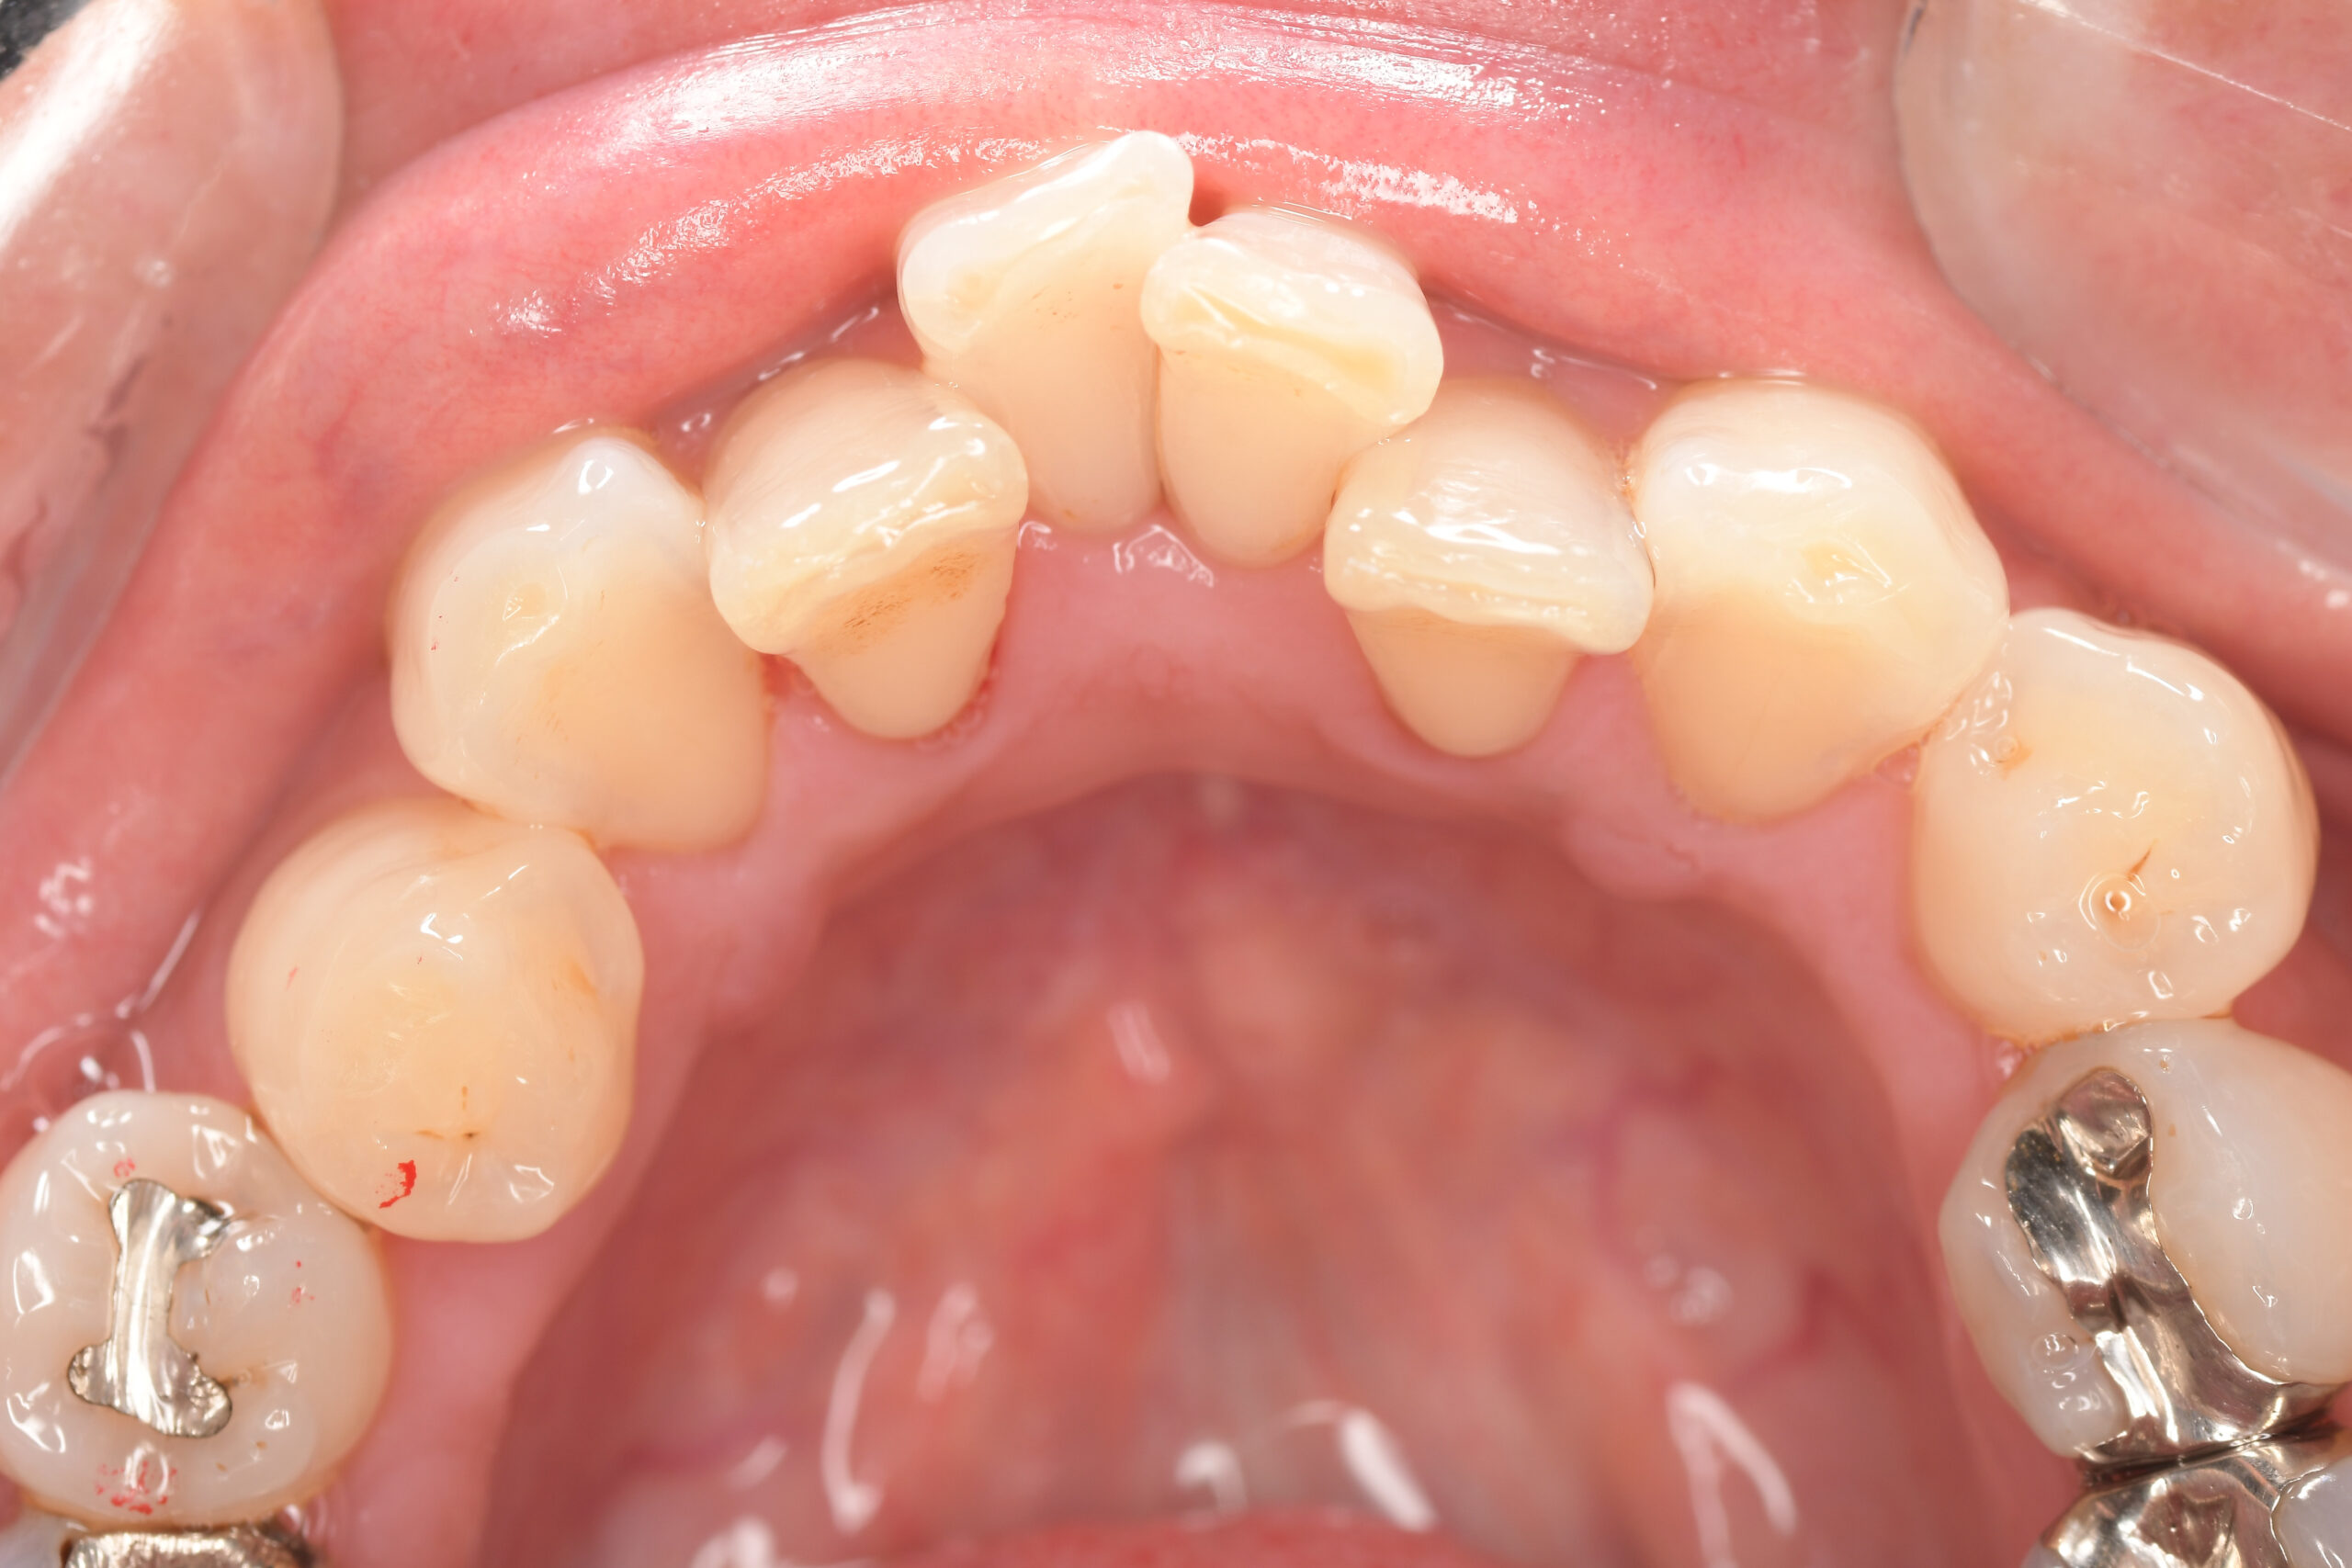

CASE 4

Before

After

基本情報

| 年齢・性別 | 52歳・女性 |

| 主訴 | クリーニングしたい |

| 治療内容 | スケーリング・PMTC |

| 治療期間 | 60分 |

| 治療費 | 約7,000円 |

| リスク・副作用 | 知覚過敏、歯肉退縮 |

| 治療方針 | 歯石とステインを除去して、今後は定期検診でのクリーニングと併せてガムピーリングやホワイトニングを行います。 |

| 担当者所見 | 歯肉の色素沈着が目立つため、ガムピーリングを行いながらホワイトニングを行うことをおすすめします。 |